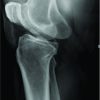

A 42-year-old male reported occasional pain in his left hip when he walked. A bilateral assessment indicated a full range of motion at the hip joints. Plain radiographs showed an osteolytic area at the femoral neck and distally adjacent osteosclerosis (Fig. 2a). Magnetic resonance imaging (MRI)revealed an osteolytic lesion with homogeneous high-signal intensity and intermediate-signal intensity in the T2- and T1-weighted images, respectively. The homogeneous signal intensity, as well as the peripheral enhancement by gadolinium, suggested that the lesion was of a cystic nature and contained serous fluid (Fig. 2b-d). Also based on MRI, in the osteosclerotic area there was a heterogeneous low-to slightly high-signal intensity on T2- and T1-weighted images, with gadolinium enhancement (Fig. 2b-d).Accordingly, the osteosclerotic lesion was diagnosed as fibrous dysplasia. The cystic lesion in the bone was a secondary bone cyst. The reported pain was judged to be caused byan impending fracture at the lesion site. The implantation of β-TCP was performed through a small 7-mm fenestration in the lateral greater trochanter. Intraoperative findings confirmed that the lesion was cystic, and that the intra-cystic content was serous, but did not contain blood. A needle biopsy from the osseous lesion was performed. Columnar-shaped β-TCP and β-TCP particles were implanted using the special funnel (7mm diameter). The histology showed irregular shaped trabeculae composed of woven bone lacking osteoblastic rimming, embedded in a cellular fibrous stroma of bland-looking spindle- or stellate-shaped cells. The histology of the fibrotic bone lesion confirmed the diagnosis of fibrous dysplasia. For 1 month postoperatively, weight bearing was allowed with a single crutch. The implanted β-TCP was gradually incorporated (Fig. 2e and f). There was no recurrence of hip pain 6 months postoperatively.